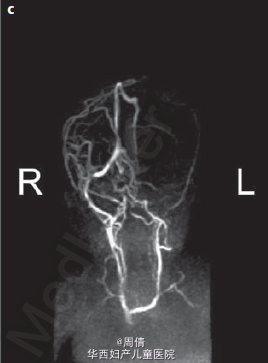

诊断为先天性腹主动脉瘤合并脑穿孔 继续妊娠,孕40周时孕妇产下一个2770g的男婴 体检提示婴儿腹部有一直径2cm的肿块 腹部CT提示降主动脉处有一直径2cm的动脉瘤 脑部CT提示左侧脑室有一囊性结构 出生第三天,MR血管造影提示胎儿期的左颈内动脉阻塞 婴儿6个月时复查腹部CT,提示降主动脉动脉瘤无明显增大,左肾动脉狭窄 因为移植如此小的血管困难太大,所以并未进行手术治疗 但是使用了VP分流器来阻止脑积水的进展